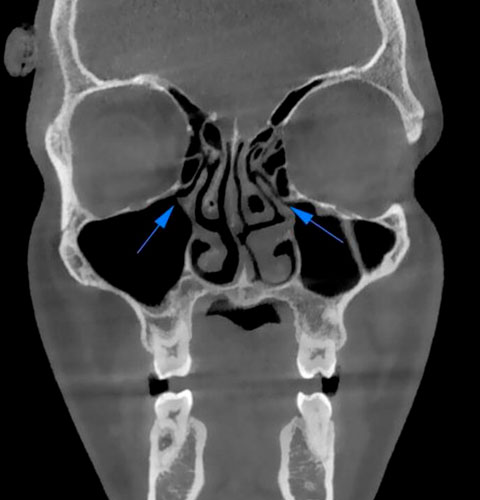

Veja exemplos de diagnósticos de imagem

- O gerador com ânodo giratório e ponto focal de 0,3 mm permite obter imagens de altíssima definição para ver detalhes e microestruturas que não podem ser investigados com dispositivos tecnológicos padrão;

- Algoritmos de reconstrução e processamento de imagem, resultado dos vinte anos de experiência da NewTom, permitem obter rapidamente imagens 2D e 3D excepcionais.